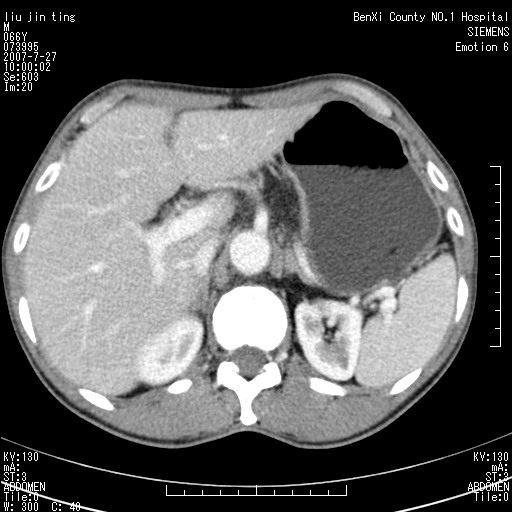

腹痛,背痛,无恶心呕吐,不黄,彩超示胰腺钩癌,ct扫描病灶平扫30-40hu,增强后动脉期40--60hu,静脉期50-68hu,真的是钩突上的么?您要试一试么?

动脉期

静脉期

沿着肠系膜上动脉呈匍匐性生长的软组织肿块,形态不规则,包绕肠系膜上动脉,呈明显强化,考虑来源于肠系膜的恶性肿瘤

沿着肠系膜上动脉呈匍匐性生长的软组织肿块,形态不规则,包绕肠系膜上动脉,呈轻-中度强化,考虑来源于肠系膜的恶性肿瘤。

钩突是正常的,只见腹膜后淋巴结的肿大,考虑淋巴瘤或转移可能。

支持!恶性纤维组织细胞瘤可能,与淋巴瘤及淋巴结转移鉴别(腹主动脉周围清晰,其他部位亦未见明显肿大淋巴结)。

考虑为腹膜后恶性纤维组织细胞瘤。